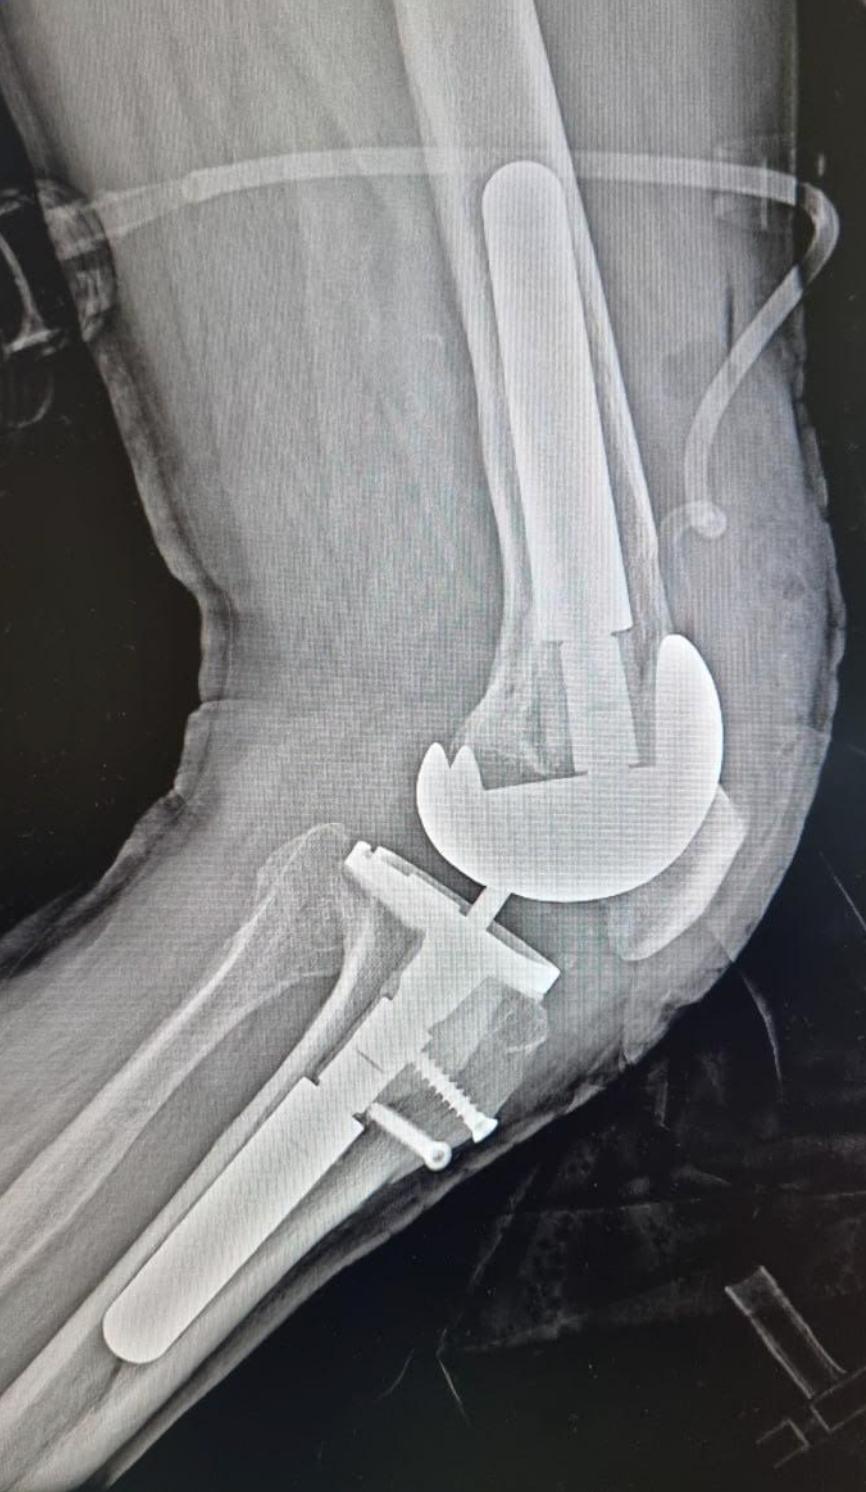

Травматологи-ортопеды Мурманского многопрофильного центра имени Н. И. Пирогова провели первую в истории медучреждения операцию по ревизионному эндопротезированию коленного сустава. Речь идёт о замене изношенного искусственного сустава на новый.

Как объяснил заведующий отделением травматологии и ортопедии Сергей Боженко, эта операция относится к категории сложнейших. «Нужно убрать старый протез и все его компоненты и установить новый. Сложность в том, что при удалении протеза всегда возникает дефицит костной ткани, который нужно заполнить специальными компонентами», — отметил врач. Процедура сопровождается длительным восстановительным периодом.